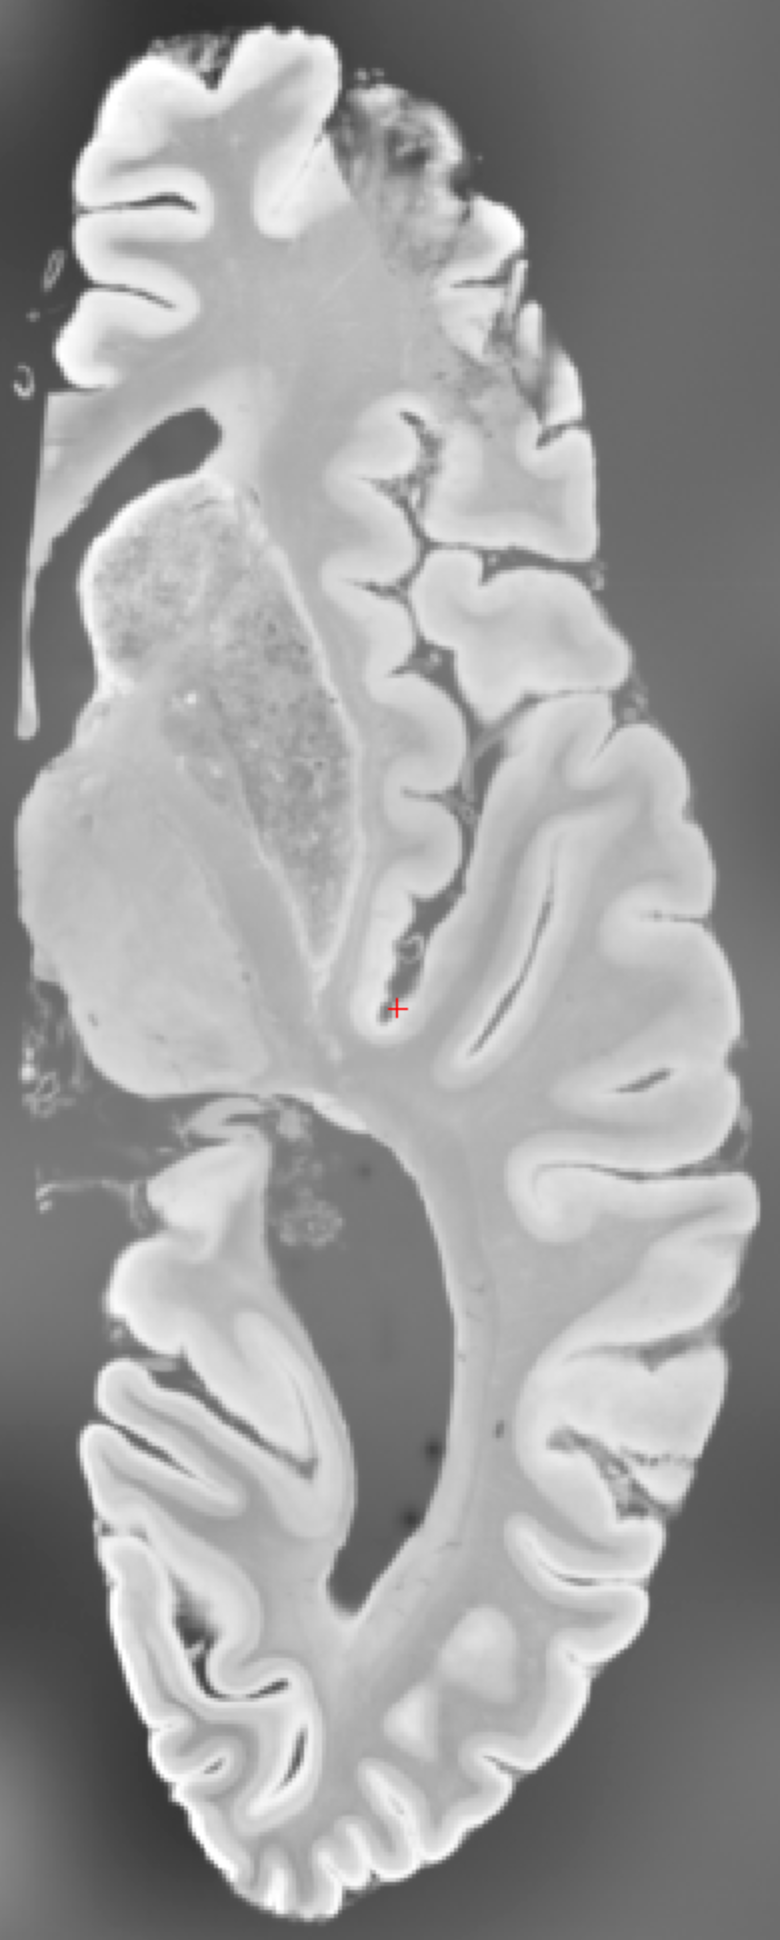

10 Qualitative Results

For qualitative results, we provide another sample from U01 in Figure 4.

![]() |

| (a) Input | (b) LR guidance | (c) GT | (d) Naive Seg | (e) Predict | (f) Regress | (g) SCCS |